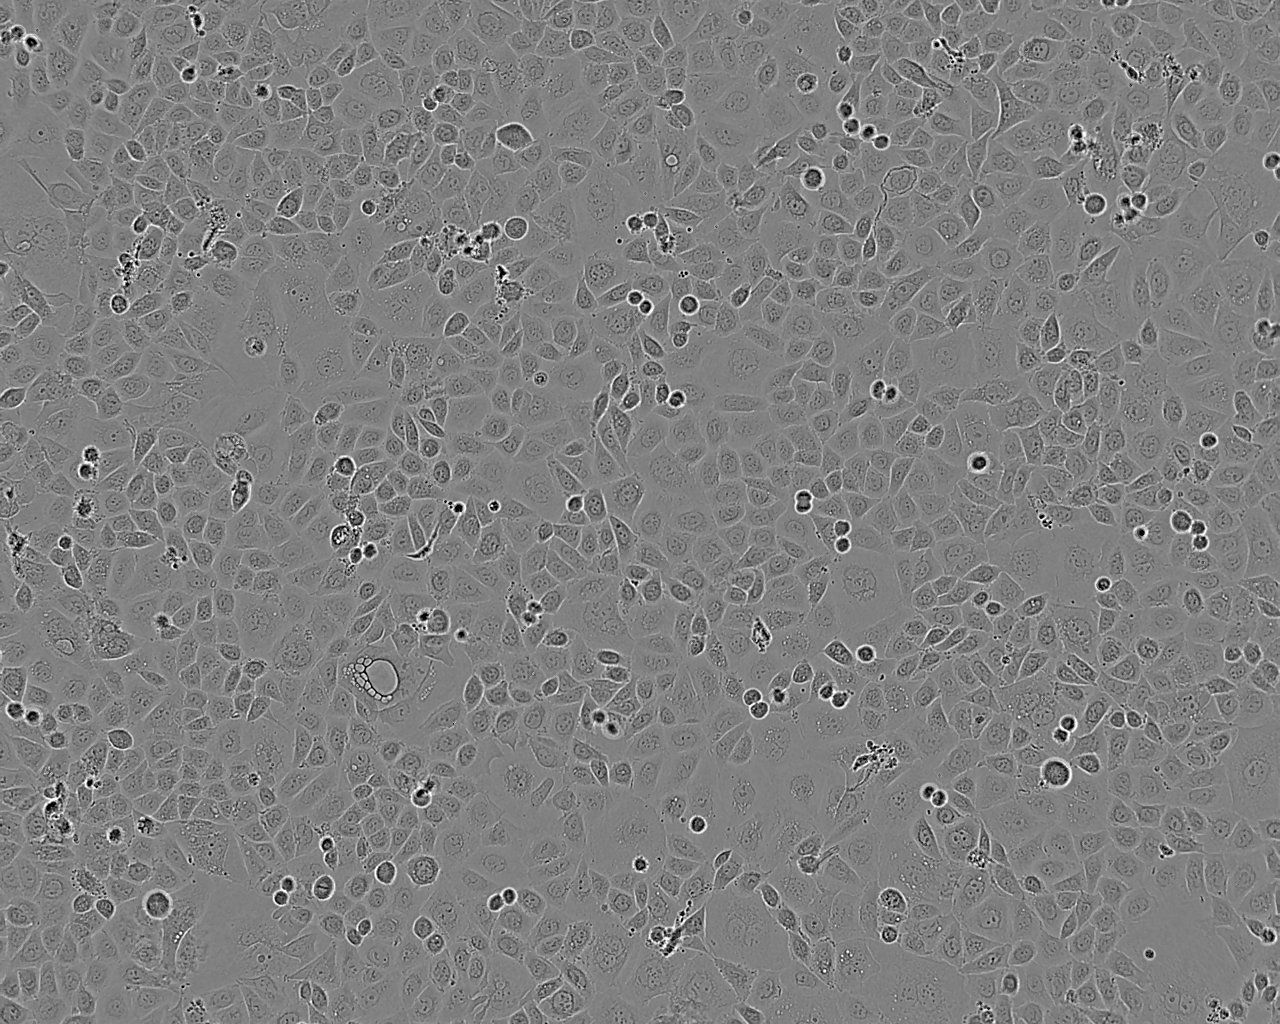

• Fu97 人胃癌细胞系

细胞形态:上皮细胞样

细胞生长:贴壁

细胞生长特性:贴壁或悬浮,详见细胞说明书部分